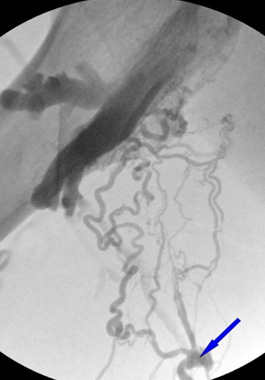

そのため、原因を正確に特定し適切な治療を行うためには、綿密な検査が不可欠です。延世ソン血管外科クリニックでは、しびれや冷えの原因を正確に特定するために、高度な検査システムを導入しています。独自の血管治療経験を持つ専門医が、大学病院レベルの最新超音波機器を利用して、深部静脈、表在静脈、穿通枝および各静脈の合流部を検査し、微小循環の血流を綿密に調べます。検査後、血管の異常によってしびれや冷えがある場合は、弱くなった静脈壁を強化し、逆流している静脈血流を正常化する治療を行います。

起始部が逆流している場合、大伏在静脈と深部静脈が合流する場所での2つの血管の角度が0度に近いほど、水平にしっかりと閉塞し、再発を防ぎます。